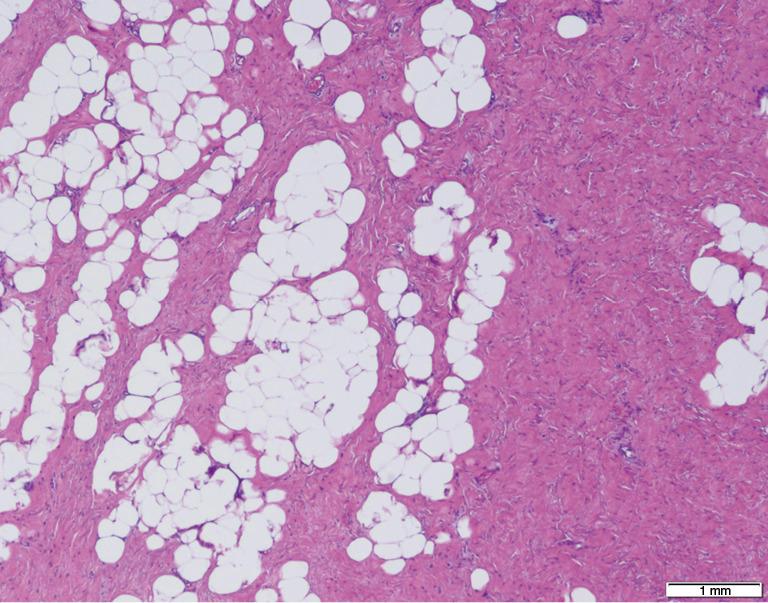

Giant gluteal lipoma presenting as sciatic hernia: a case description.